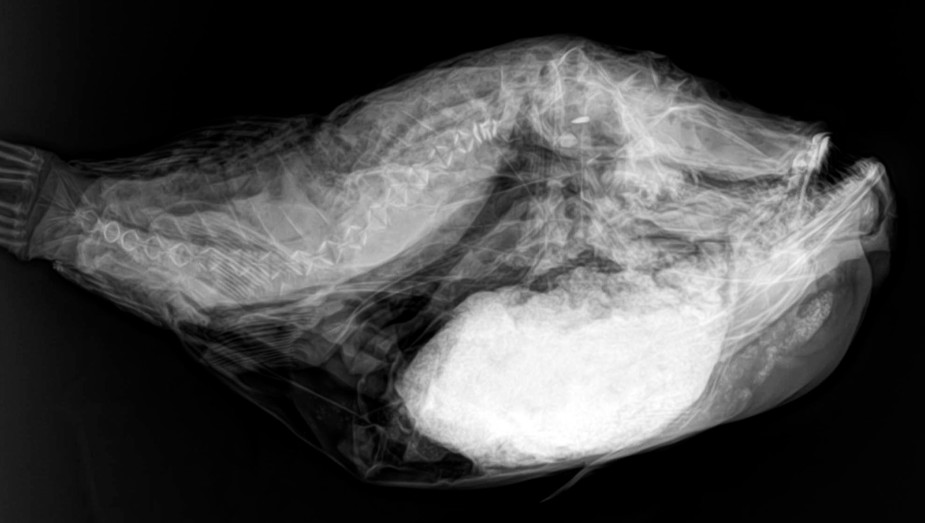

Desde el descubrimiento de los rayos “X” y las placas radiográficas por Wilhelm Conrad Roentgen y su posterior difusión a través de la Asociación Físico médica de Wurzburg el 28 de diciembre de 1895, que fue la primera asociación que habló de los nuevos rayos que podían penetrar el cuerpo y fotografiar los huesos, ha habido muchos cambios tanto en la forma de obtener, procesar e incluso en la forma de visualizar, manejar y almacenar las placas radiográficas.